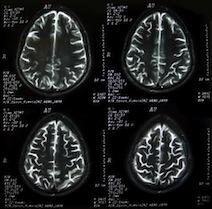

Brain injuries can range from mild to severe. Below are the most common types of brain injuries:

In simplest terms, the brain is divided into four main lobes and the brain stem. Each part of the brain has a separate function and any type of injury can result in serious impairments. Below is a list of the different parts of the brain and their essential functions: